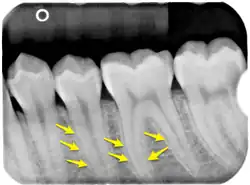

Die häufigste und seit vorgeschichtlicher Zeit nachweisbare[14] Krankheit der Zähne und des Menschen überhaupt ist die Zahnkaries (Zahnfäule). In Deutschland ist nur ca. ein Prozent der Erwachsenen kariesfrei, hat also naturgesunde Zähne.[15] Die Bemühungen mittels Gruppenprophylaxe und Individualprophylaxe führen zu immer besserer Zahngesundheit, insbesondere von Kindern und Jugendlichen, die mittels des DMFT-Index gemessen wird. Auch Erkrankungen des Zahnhalteapparats (siehe Zahnfleisch, Parodontitis) sind häufig. Ein seltenes Krankheitsbild ist die Tuberkulose der Zähne, bei der es durch zumeist bronchogene Streuung zu Entwicklung von tuberkulösen Zahngranulomen kommen kann. Orale, meist übersehene Befunde finden sich bei 1,4 % der an Tuberkulose Erkrankten.[16]

Zahnbefestigung

Als Wurzelhaut (Syn.: Periodontium) wird das Bindegewebe des Zahnhalteapparates bezeichnet. Diese Sharpey-Fasern, zum Periost gehörende Kollagen-Faserbündel, die in der Knochengrundsubstanz befestigt sind, bilden die Verbindung zum Wurzelzement des Zahnes. An ihnen ist der Zahn federnd befestigt und überbrückt den wenige Zehntel Millimeter breiten Spalt (Periodontalspalt) zwischen dem Zahnzement der Zahnwurzel und der knöchernen Wand des Zahnfachs (Alveole), der Lamina dura. Am Zahnhals wird der Periodontalspalt durch den supraalveolären Faserapparat (frühere Bezeichnung: Ligamentum circulare) abgedichtet.